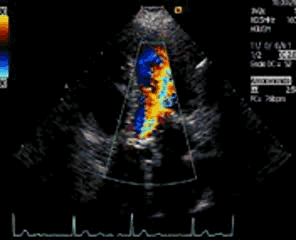

102. El Doppler.Nociones Básicas. Doppler Color.